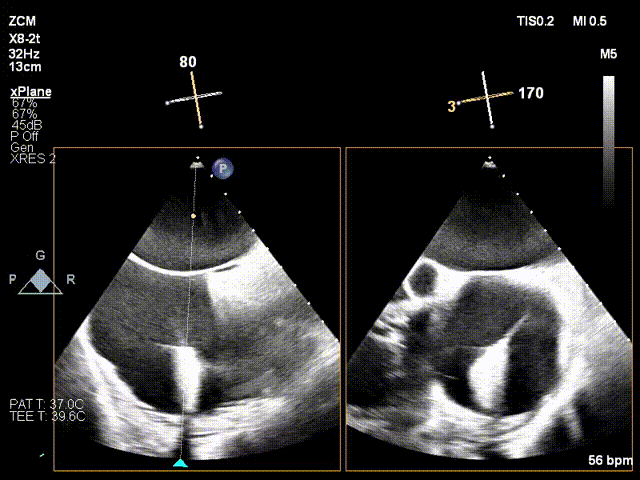

4.打开夹臂调整Orientation后贴靠瓣环。

打开夹臂后调整轴向并贴靠瓣环